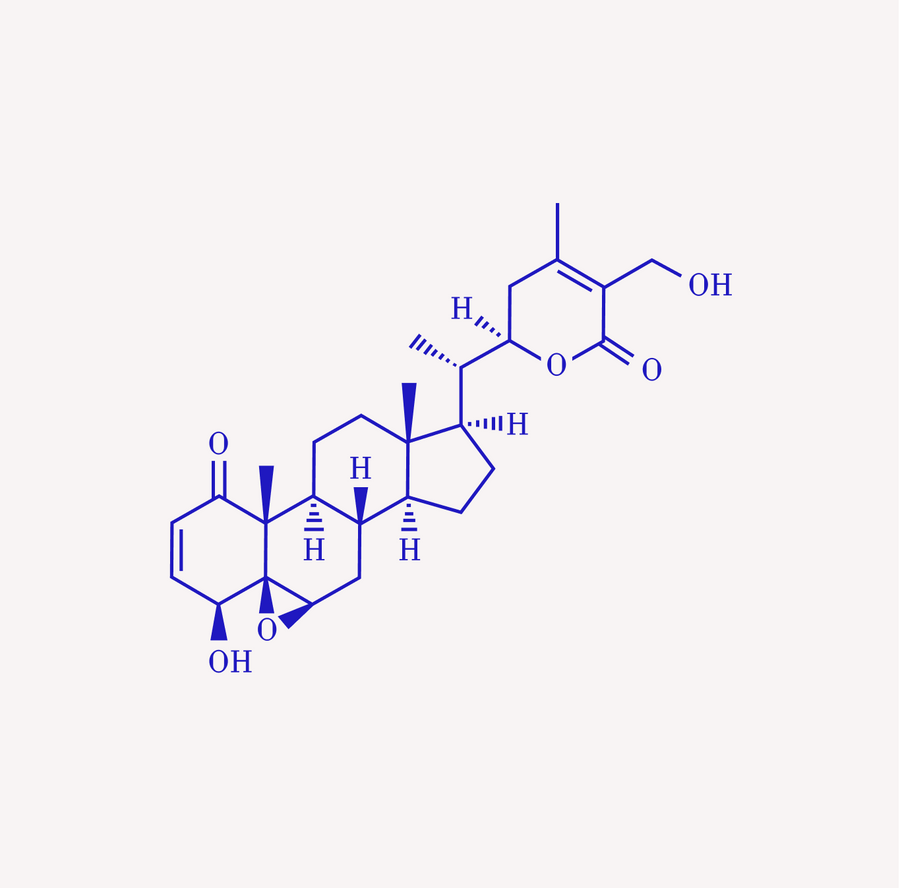

Ashwagandha & Rhodiola

Regulate cortisol, improve stress resilience, and energy.

Akhgarjand C, Asoudeh F, Bagheri A, Kalantar Z, Vahabi Z, Shab-Bidar S, Rezvani H, Djafarian K. Hat eine Ashwagandha-Ergänzung eine positive Wirkung auf die Behandlung von Angst und Stress? Eine systematische Übersichtsarbeit und Metaanalyse randomisierter kontrollierter Studien. Phytother Res. 2022 Nov;

Speers AB, Cabey KA, Soumyanath A, Wright KM. Auswirkungen von Withania somnifera (Ashwagandha) auf Stress und die stressbedingten neuropsychiatrischen Störungen Angst, Depression und Schlaflosigkeit. Curr Neuropharmacol. 2021;

Auswirkungen von Withania somnifera auf den Cortisolspiegel bei gestressten Menschen: Eine systematische Überprüfung.

Della Porta M, Maier JA, Cazzola R.Nährstoffe. 5. Dezember 2023 Arumugam V, Vijayakumar V, Balakrishnan A, B Bhandari R, Boopalan D, Ponnurangam R, Sankaralingam Thirupathy V, Kuppusamy M. Auswirkungen von Ashwagandha (Withania Somnifera) auf Stress und Angst: Eine systematische Überprüfung und Metaanalyse. Entdecken (NY). 2024 Nov.-Dez.;

Gopal S, Ajgaonkar A, Kanchi P, Kaundinya A, Thakare V, Chauhan S, Langade D. Wirkung eines Ashwagandha-Wurzelextrakts (Withania Somnifera) auf klimakterische Symptome bei Frauen während der Perimenopause: Eine randomisierte, doppelblinde, placebokontrollierte Studie. J Obstet Gynaecol Res. 2021 Dez;

Ivanova Stojcheva E, Quintela JC. Die Wirksamkeit von Rhodiola rosea L.-Präparaten bei der Linderung verschiedener Aspekte des Lebens – Stresssymptome und stressbedingte Zustände – ermutigende klinische Beweise. Moleküle. 17. Juni 2022;

Cropley M, Banks AP, Boyle J. Die Wirkung von Rhodiola rosea L.-Extrakt auf Angst, Stress, Kognition und andere Stimmungssymptome. Phytother Res. 2015 Dez;

Calabrese EJ, Dhawan G, Kapoor R, Agathokleous E, Calabrese V. Rhodiola rosea und Salidrosid induzieren häufig Hormesis, mit besonderem Fokus auf Langlebigkeit und Neuroprotektion. Chem Biol Interact. 1. August 2023;